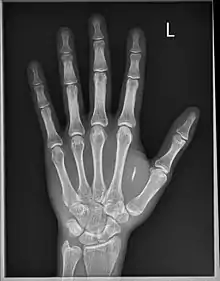

Le , le scientifique Britannique Mark Gasson s'est fait implanter chirurgicalement un dispositif RFID avancé au sein d'une capsule de verre dans la main gauche. En , l'équipe de Mark Gasson démontra comment un virus informatique pourrait infecter sans contact son implant et ensuite être transmis à d'autres systèmes[3]. Mark Gasson établit donc qu'en implémentant de la technologie, la séparation entre l'homme et la machine devient alors théorique, celle-ci étant alors perçue par l'organisme comme faisant partie intégrante du corps. En raison de cette évolution dans notre compréhension de ce qui constitue notre corps et ses limites, il est alors crédité comme étant le premier homme infecté par un virus informatique. Il n'a pas l'intention de retirer son implant[4].

Mikey Sklar se fait implanter une puce dans la main gauche et filme la procédure[6].